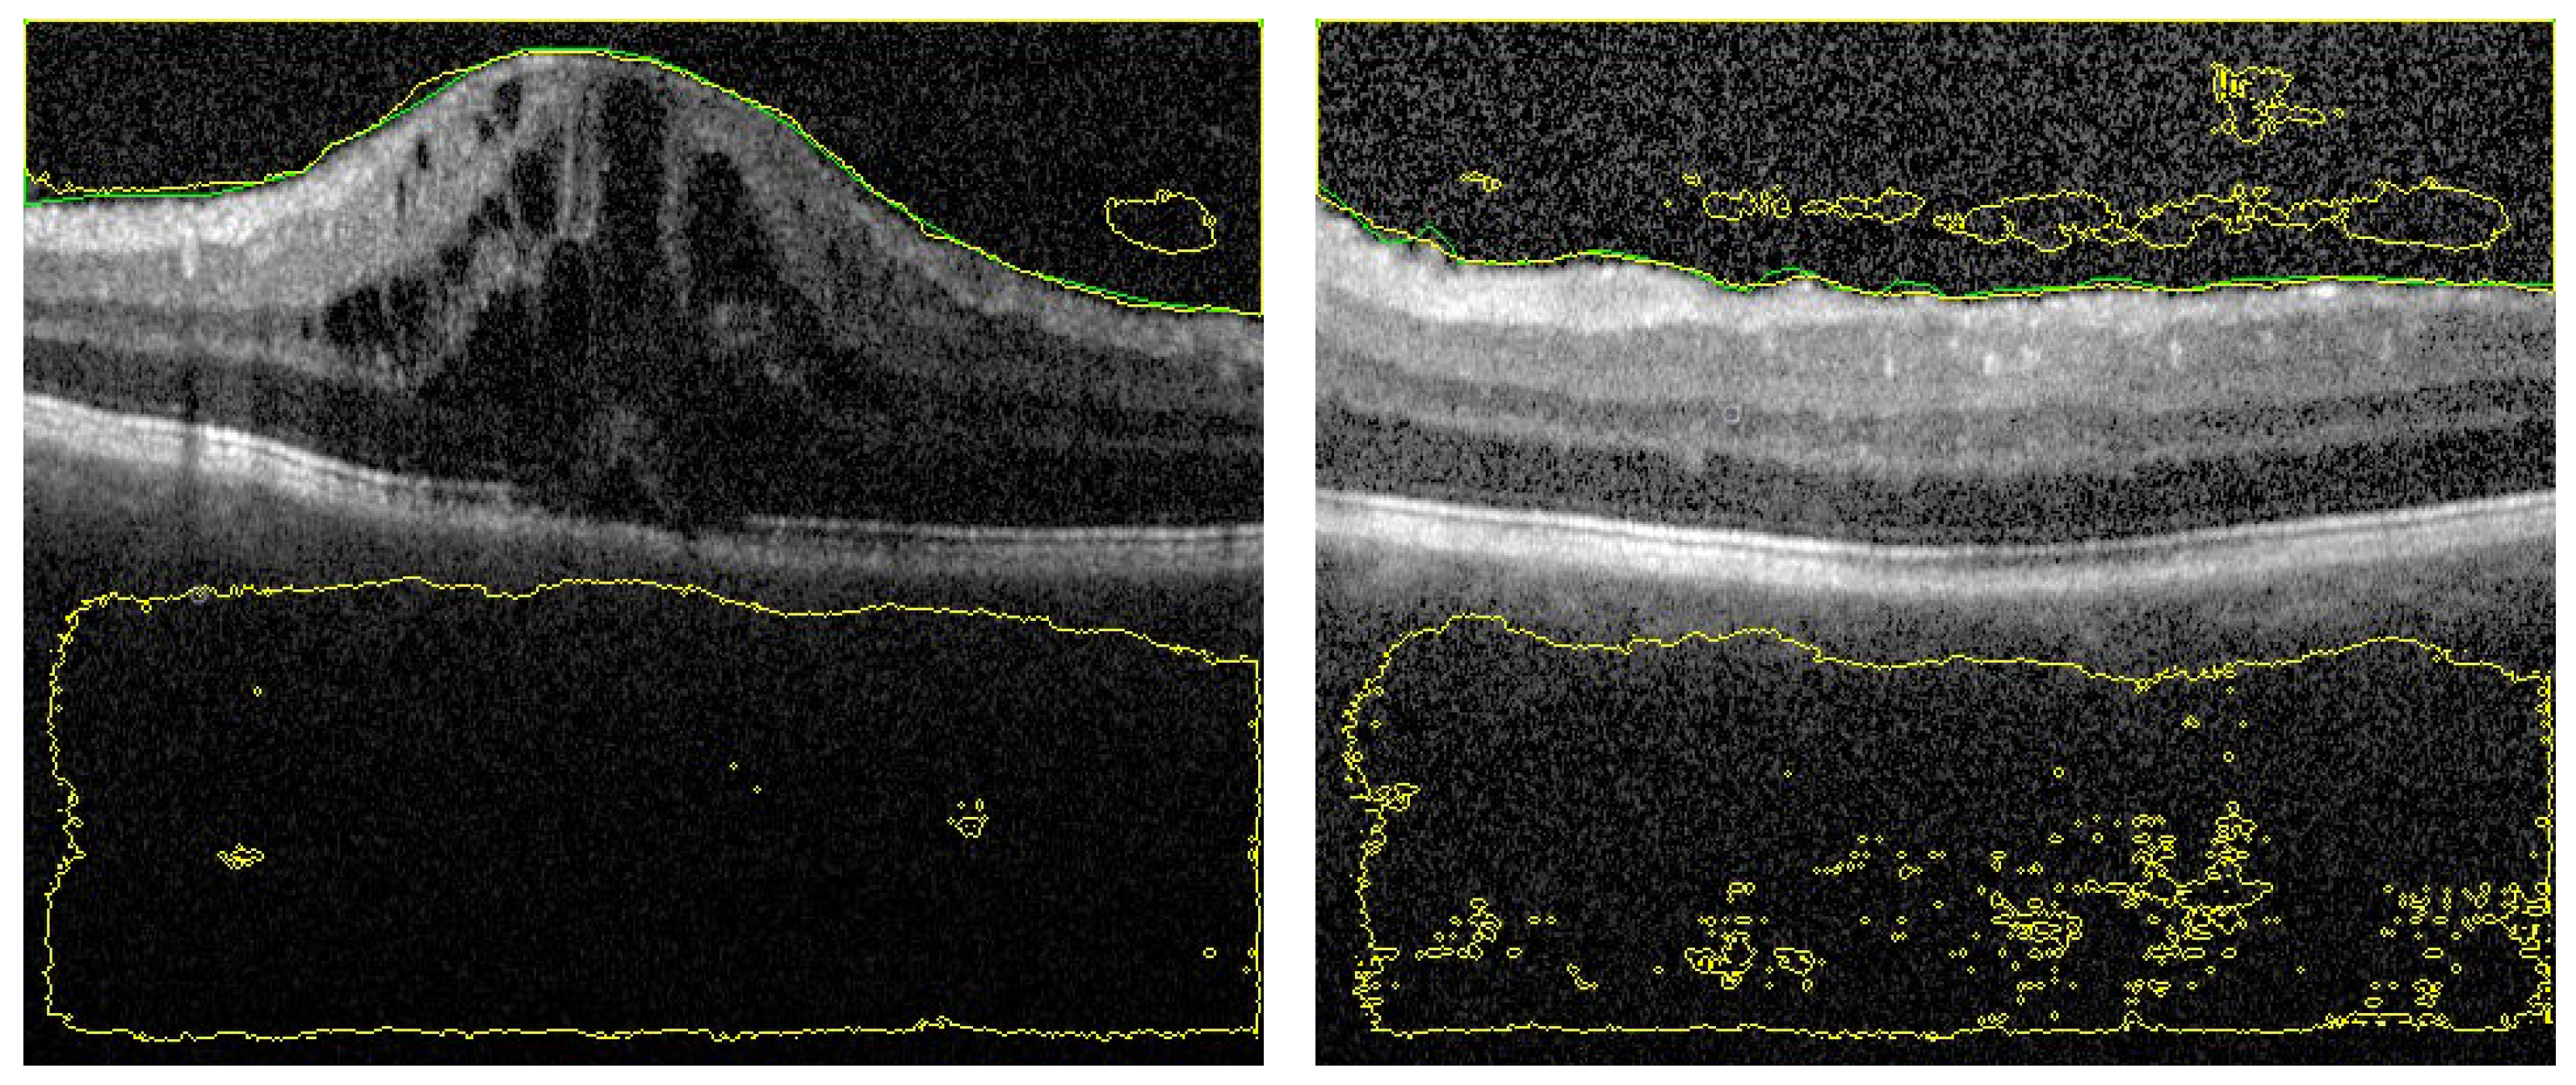

3.2. Fused Image Construction

3.3. Overall Segmentation Evaluation

3.4. Ablation Study